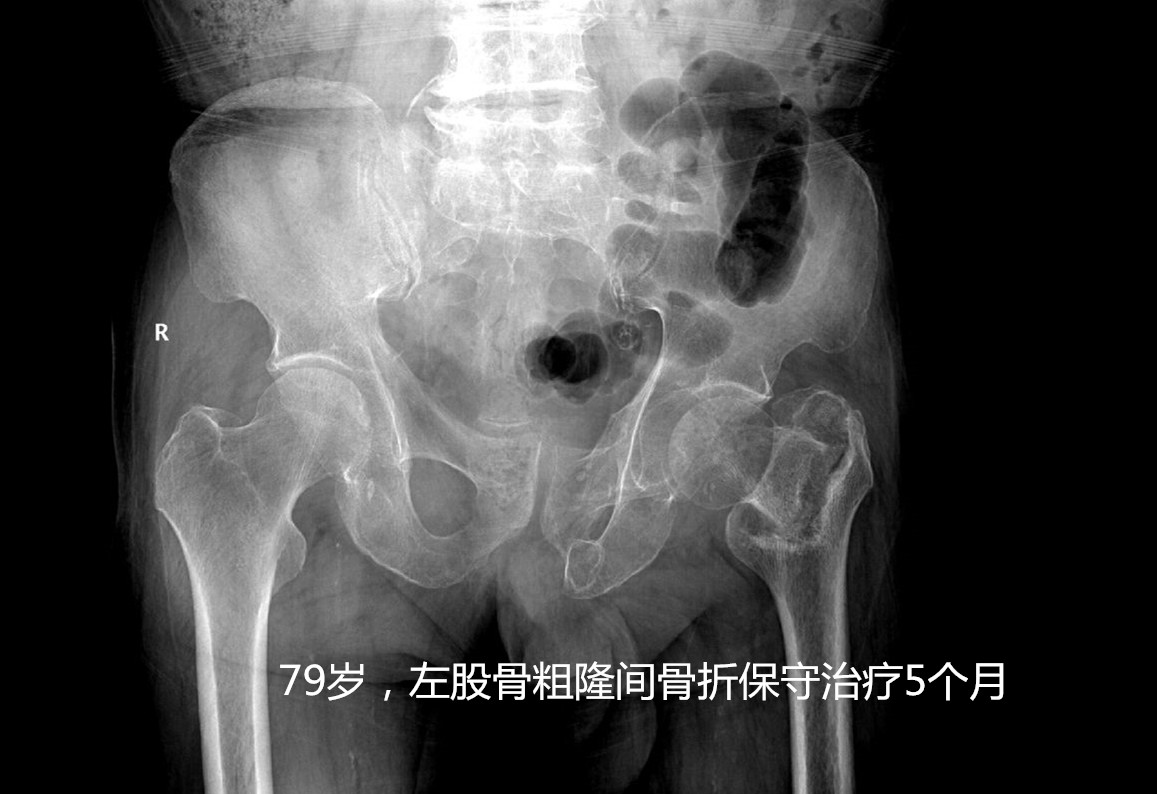

答案就是指 老年人髋部骨折 ,也就是东北话常说的“ 胯骨轴摔坏了 ”,包括股骨颈及粗隆间骨折。这个部位骨折后病人因轻微活动便会诱发较剧烈的疼痛,通常无法坐起、翻身困难,需长期卧床,只有一少部分骨折无移位或者骨折断端嵌插的病人,经2-3个月的卧床后出现骨折愈合后可能恢复行走功能,其余病人可能因骨折不愈合、畸形愈合等丧失行走功能。长期卧床面临着肺内感染、坠积性肺炎、褥疮、下肢静脉血栓、泌尿系感染等并发症, 据统计约50%的患者因卧床出现相关并发症在1年内死亡 ,所以被称作“人生最后一次骨折”。

这种骨折出现了怎么治疗呢?其治疗方法分为手术内固定治疗(如空心钉、PFNA、INTER- tan等等)或者人工关节置换手术治疗。